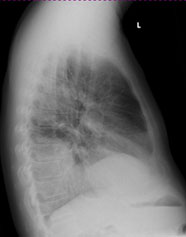

Ein 68-jähriger Patient mit chronischer Niereninsuffizienz und hypertensiver Herzerkrankung klagt akutell über zunehmende Dyspnoe. Sie veranlassen ein Thoraxröntgen.

Thorax pa

Thorax seitlich

Welcher Befund liegt vor? (mehrere richtige Antworten möglich)